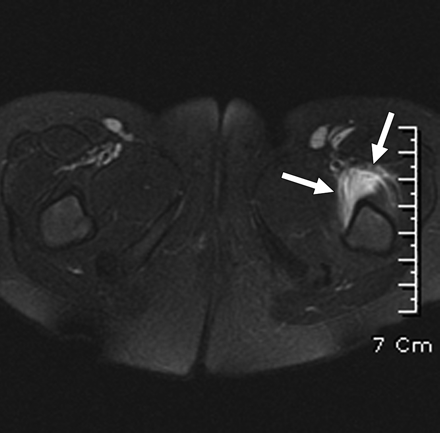

Resonancia magnética

• Un estudio de Lee y cols. propone que se puede diferenciar sinovitis transitoria de artritis séptica mediante resonancia magnética. Este estudio encontró que la artritis séptica presenta alteraciones de la intensidad de la señal en la médula de la cadera afectada. Sin embargo, hacen falta más estudios para confirmar este método de diagnóstico no invasivo (imagen 4).

RM con alteración de señal en médula ósea.

Imagen 4: Alteraciones de señal en médula ósea observadas en resonancia magnética, compatibles con artritis séptica.